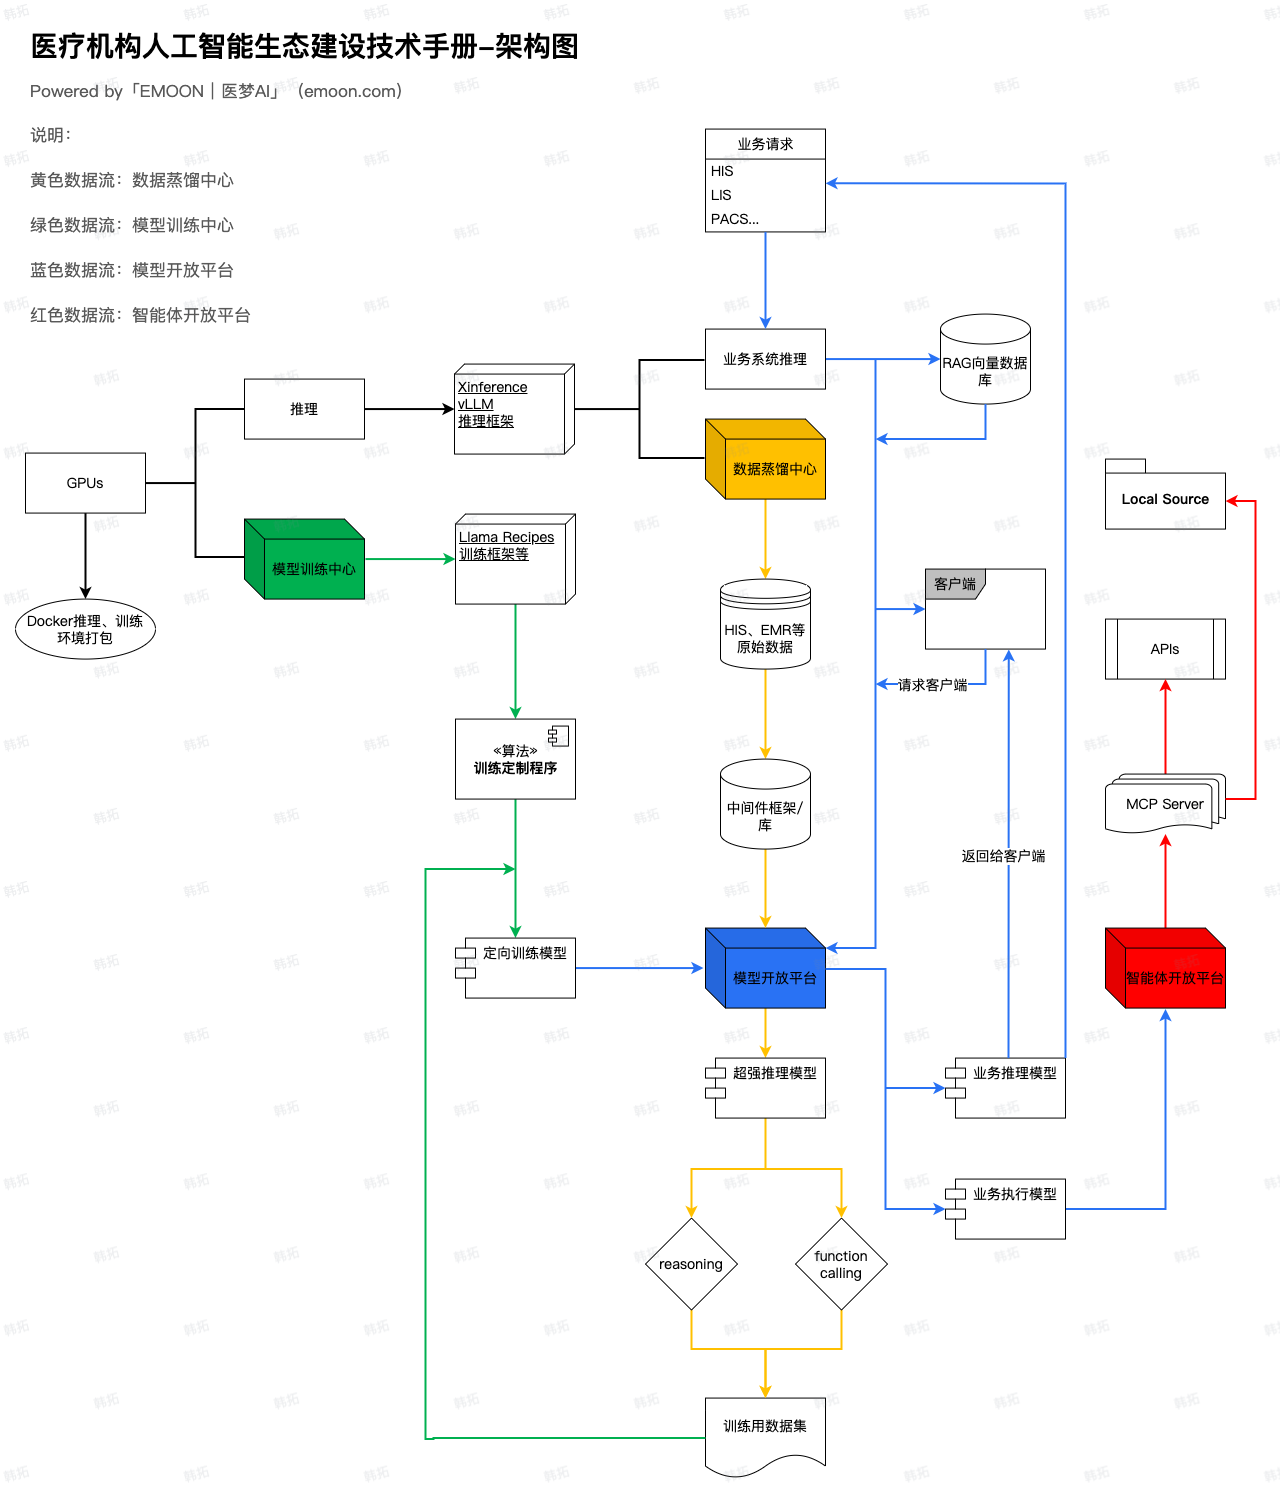

基于医疗机构对 AI 的需求已从单点实验进步至全院级协同,医疗专精模型训练的需求日益增强,医梦 AI 模型训练中心为专精模型训练搭建模型训练工程,通过对模型预期能力的多轮训练,为医疗机构训练专属业务能力的专精模型。

模型训练中心通过对模型预期能力的算法开发,以及模型训练框架的深度优化,定向开发搭配模型蒸馏中心数据集的模型训练程序,支持reasoning、function calling等推理、智能体扩展训练,训练出具备深度理解业务的私有转向模型。

模型训练中心作为AI生态中专精模型训练的核心,与数据蒸馏中心、模型开放平台均有数据流交互,如下图中绿色数据流所示: